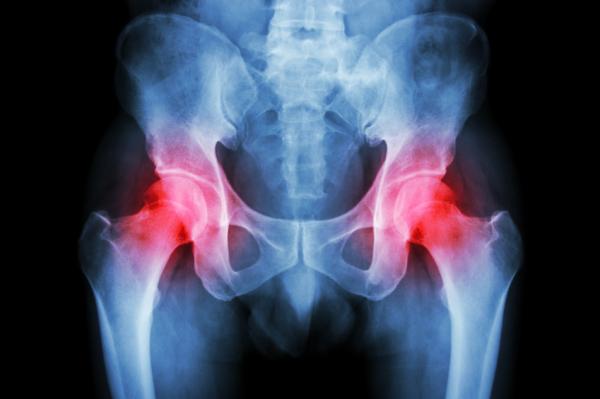

La cadera es una zona en la que es común que muchas personas tengan molestias, pudiendo focalizarse en un lado y siendo frecuente el lado derecho. Este síntoma puede deberse a múltiples enfermedades, que van desde una rotura hasta problemas comunes de espalda o patologías más graves.

Dolor en la cadera derecha por problemas de huesos

A veces, el dolor en la cadera derecha no tiene más explicación que un problema de huesos. Esto sucede más frecuentemente en personas mayores en las que ya se va produciendo osteoporosis, es decir, la descalcificación de los huesos y estos están más frágiles. Al ser la cadera fundamental para la movilidad de la persona, se van haciendo esfuerzos sobre ella que terminan en la aparición del dolor.

• La rotura de la cadera es una de las más habituales. Este tipo de fracturas es más común en las personas mayores por el desgaste de los huesos y su mayor fragilidad, porque esto favorece su rotura con más facilidad. Este tipo de dolor se reconoce porque suele ser bastante intenso y aparece de repente, normalmente, tras una caída.

• Las infecciones en los huesos, o también en las articulaciones, de la cadera derecha son otros de los motivos que causan el dolor. Lo más habitual es que estos procesos infecciosos sean originados por bacterias u hongos, que traspasan la piel, llegan por los músculos cercanos a estos huesos o bien, por la sangre. Este tipo de casos es más habitual en personas con lesiones recientes en esa zona o bien que son diabéticas.

• La artritis es otra de las enfermedades que puede notarse en la cadera derecha, aunque en este caso el dolor se siente también en el muslo y en la ingle. Siempre coincide con el área en el que están las articulaciones.

• La osteonecrosis también explica el dolor en la cadera derecha. Esta enfermedad se produce por una carencia en la llegada del flujo sanguíneo al hueso.

• La rotura del cartílago de la cadera derecha es otra de las causas que justifican este dolor. Normalmente, se produce por su desgaste o por algún traumatismo en los huesos de esta zona. También puede suceder por enfermedades degenerativas de las articulaciones o por el desgarro del labrum, que es como una almohadilla que se encarga de proteger la articulación de la cadera.